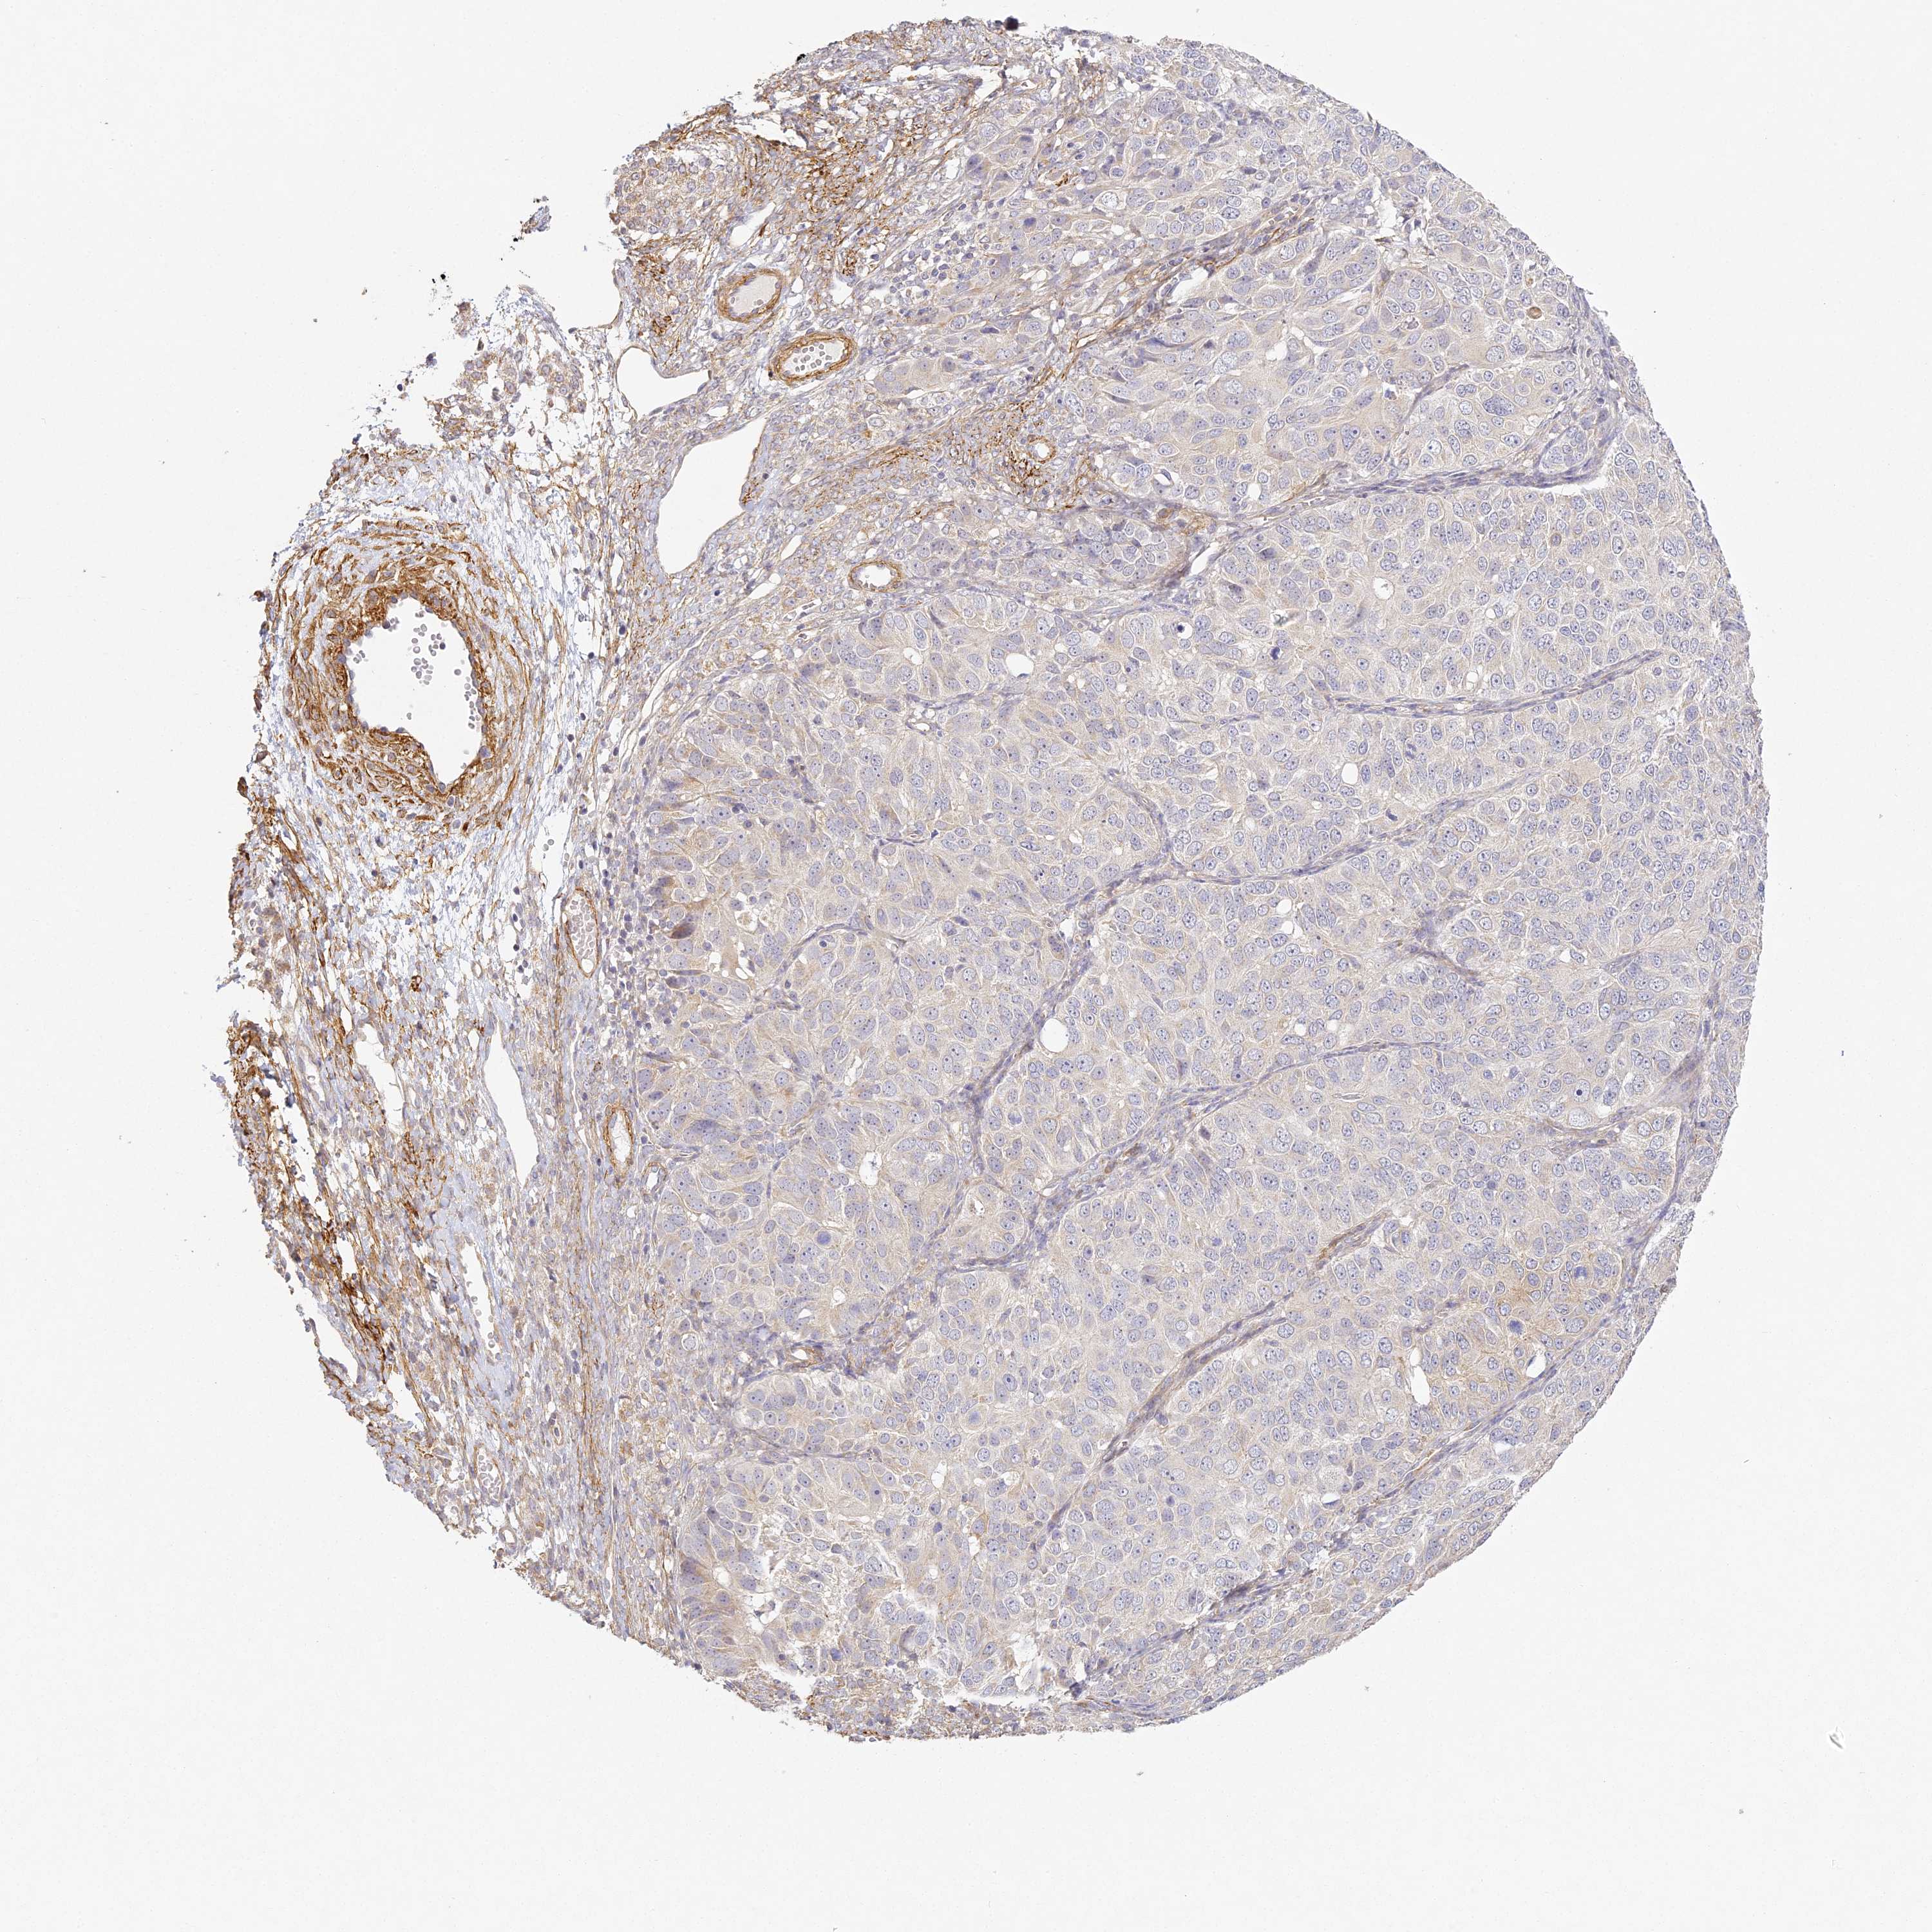

OVARIAN CANCER - Protein expressioni

A mouse-over function shows sample information and annotation data. Click on an image to view it in a full screen mode. Samples can be filtered based on level of antibody staining by selecting one or several of the following categories: high, medium, low and not detected. The assay and annotation is described here.

Note that samples used for immunohistochemistry by the Human Protein Atlas do not correspond to samples in the TCGA dataset.

Antibody stainingi

Antibody staining in the annotated cell types in the current human tissue is reported as not detected, low, medium, or high, based on conventional immunohistochemistry profiling in selected tissues. This score is based on the combination of the staining intensity and fraction of stained cells.

Each image is clickable and will lead to virtual microscopy that enables deeper exploration of all samples and also displays staining intensity scores, fraction scores and subcellular localization as well as patient and tissue information for each sample.

Antibody HPA035900

Antibody HPA035901

Cystadenocarcinoma, serous, NOS